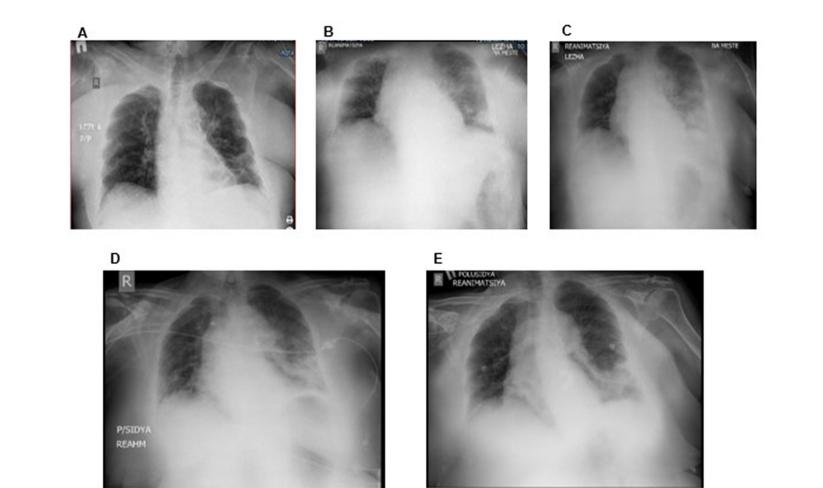

常规实验室检查结果:CBC显示白细胞增多形式的以下变化,白细胞公式向左刺移,ESR升高,轻度贫血。患者尿检也显示炎症改变。血液生化显示肾功能受损,表现为肌酐和尿素水平升高,肝转氨酶轻度升高和低蛋白血症。整个期间止血系统无明显异常,凝血结果偶见轻微的低凝倾向。入院时,胸部X线片显示心脏肿大,肺部未见明显变化(图A)。入院11小时后,患者呼吸系统检查有改变,胸部对照X线片显示左侧肺炎(图B)。患者紧急转至ICU,血气分析示低氧合指数(270.3mm Hg)。PCR检验COVID-19呈阴性。在动力学方面,患者住院第3天,根据胸部X光片的结果,肺炎病情进展,需要加强抗生素治疗(图C)。在脓毒症的综合治疗中加入持续输注美罗培南(Santo, Kazakhstan, Shymkent)。在住院的第五天,一个胸部x光片显示上述情况的积极变化(图D)。住院第11天,作为综合治疗的一部分,连续输注美罗培南6天后,胸片显示左侧肺炎消退(图E)。

图A-E    连续输注美罗培南后胸部x线动态:第1天CXR (A),第2天CXR (B),第3天CXR (C),

第5天CXR (D),连续输注美罗培南6天后(住院第11天)CXR (E)